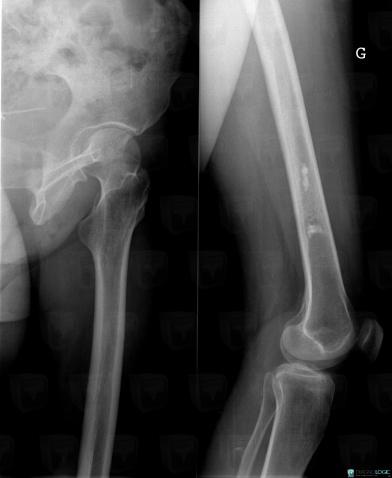

Infarctus osseux, Fémur -inférieur, Radio

Voici les informations spécifiques à l'image clé ci dessus:

- Diagnostic Infarctus osseux, Localisation(s) Fémur - 1/3 inférieur, comportant les gammes Condensation localisée unique